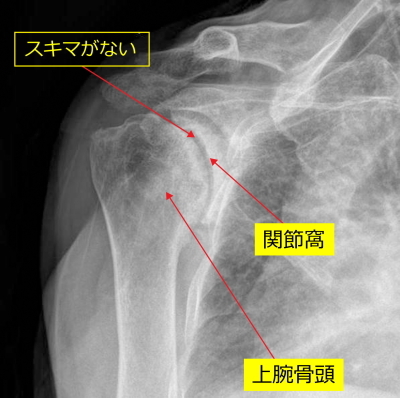

正常

上腕骨頭に丸みがあり、関節窩と上腕骨頭にすきまがあります。

手術前のレントゲン

上腕骨の変形が強い所見がみられます。上腕骨頭の丸みがなくなっています。